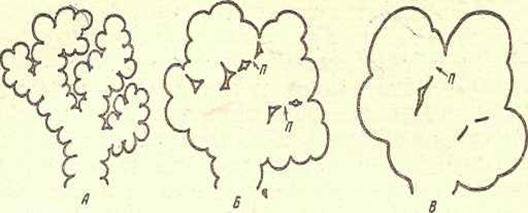

<Эмфизема ><лёгких ><— ><«вздутие». ><Группы ><альвеол ><сливаются ><в ><одну> <из-за ><разрушения ><межальвеолярных ><перегородок, ><образуя ><большие> <пузыри. >< >< >< ><Это >< >< ><приводит >< >< ><к >< >< ><резкому >< >< ><уменьшению >< >< ><дыхательной> <поверхности.

Рис. 12. >Развитие эмфиземы легкого (схема).

А— разветвление альвеолярного хода с нормальными альвеолами; Б—расширение альвеолярных ходов и пор (п); В- —альвеолярные ходы превратились в

Пузыри стенки между ними атрофировались